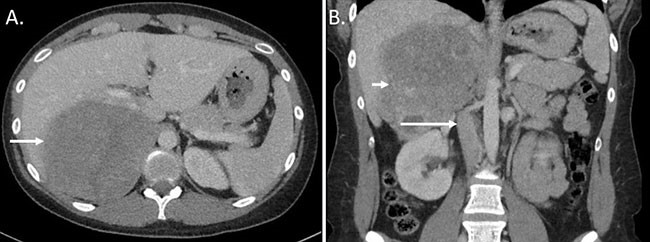

Biochemical evaluation demonstrated an elevated midnight salivary cortisol of 510 ng/dL (normal <100 ng/dL), suppressed 6:30 AM serum ACTH <1 pg/mL (normal 6–76 pg/mL), elevated DHEA-S of 350 mcg/dL (normal 44–332 mcg/dL), and hypokalemia with serum potassium 2.8 mmol/L (normal 3.4–5.0 mmol/L). Low- and high-dose dexamethasone suppression tests were consistent with autonomous adrenal secretion of cortisol. Serum renin, aldosterone, and metanephrines were within normal limits. A CT scan of the abdomen demonstrated an 11-cm heterogenous right adrenal mass (Figure 2), abutting the inferior vena cava (IVC), right kidney, and right hepatic lobe and exerting mass effect on all adjacent structures, without evidence of discrete invasion or distant metastases, and a normal appearing left adrenal gland.

Figure 2: CT abdomen and pelvis with intravenous contrast. A.) Axial images demonstrating an 11 cm, heterogenous adrenal mass (white arrow). B.) Coronal images showing the tumor (short white arrow) abutting the inferior vena cava (long white arrow), right hepatic lobe, and right kidney.